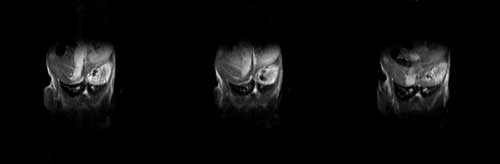

小鼠动物成像实验数据(腹部成像)

小鼠全身成像伪彩色图